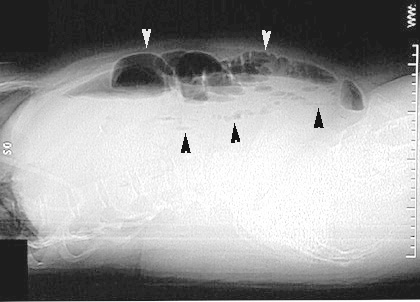

Small bowel obstruction

• Cross lateral view shows multiple dilated fluid filled loops of bowel with air fluid levels.